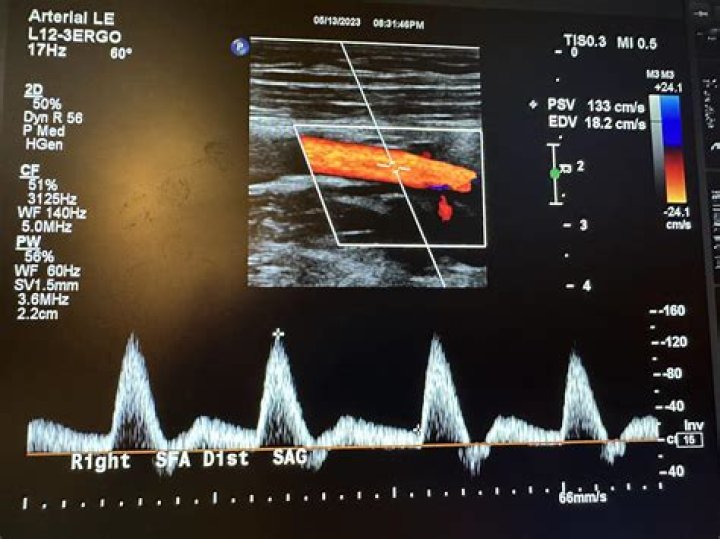

How is an arterial Doppler performed?

The test is done in the ultrasound or radiology department, a hospital room, or in a peripheral vascular lab. During the exam: A water-soluble gel is placed on a handheld device called a transducer. This device directs high-frequency sound waves to the artery or veins being tested.

Lower extremity arterial Doppler testing is noninvasive and painless. Using ultrasound technology and blood pressure cuffs, your doctor will be able to detect any narrowed or blocked blood vessels, as well as any arteries that have abnormal blood flow.

A Doppler ultrasound is a noninvasive test that can be used to estimate the blood flow through your blood vessels by bouncing high-frequency sound waves (ultrasound) off circulating red blood cells. A regular ultrasound uses sound waves to produce images, but can’t show blood flow.